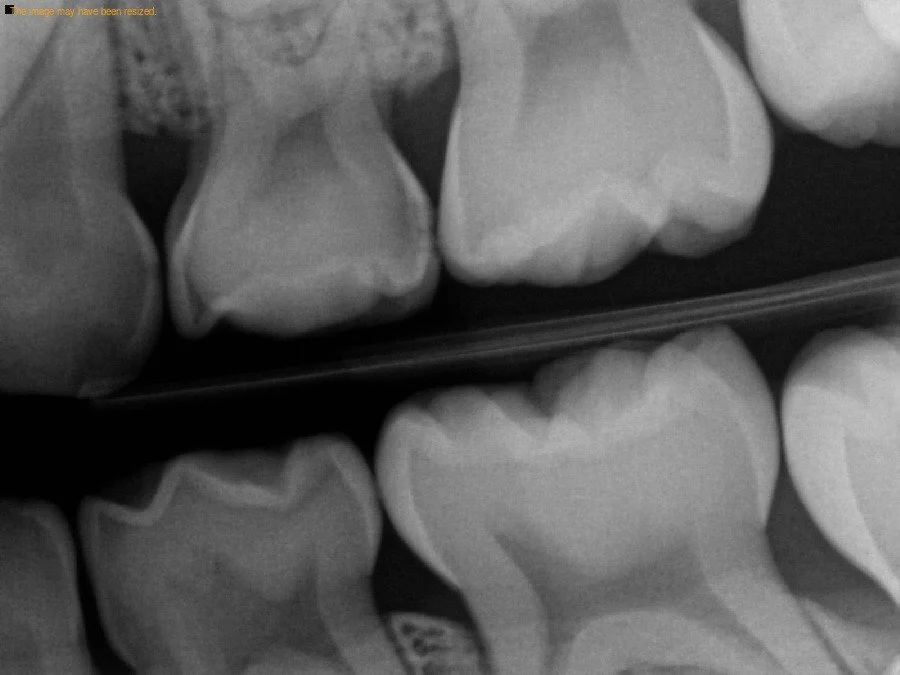

Because one of the most common places for cavities to hide is between the back teeth, bitewing x-rays allow us to see areas a visual exam simply can’t. Some children have no visible signs of decay, yet x-rays reveal significant cavities that would otherwise go unnoticed until they become painful or require more complex treatment. Catching decay early helps us keep baby molars (important for chewing and guiding permanent teeth) healthy until they naturally fall out around ages ten and twelve.

Bitewing